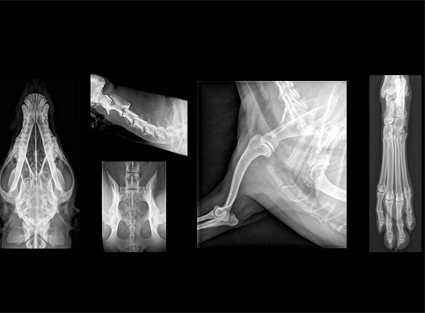

Radiología Digital en imágenes

- Imágenes de alta resolución

- Resultados rápidos

- Almacenamiento digital de estudios

- Envío de resultados por correo o WhatsApp

Radiología para Mascotas Exóticas

- Aves

- Reptiles

- Roedores

- Pequeños mamíferos